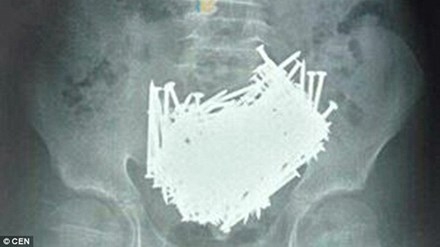

Vừa qua, sau khi chụp CT cho một cậu bé 15 tuổi, các bác sĩ ở Trung Quốc hoảng hốt khi thấy có tới 200 cái đinh nằm trong bụng.

Cậu bé nói trên đến từ Ji’an, tỉnh Giang Tây, Trung Quốc. Bất ngờ bị đau bụng dữ dội hôm 6/6 nhưng bố mẹ em chỉ nghĩ em bị cảm lạnh. Họ đưa em đến bệnh viện kiểm tra và kết quả khiến các bác sỹ sửng sốt.

Sau khi chụp CT, các bác sĩ thấy rất nhiều dị vật trong bụng bé. Các bác sĩ ngay lập tức đưa em tới phòng phẫu thuật, lấy ra hơn 200 chiếc đinh, tăm xỉa răng, đá và tiền xu trong bụng em.

Họ cho biết, trong suốt nhiều năm làm nghề y, chưa bao giờ họ thấy một ca tương tự như vậy.

Cậu bé sau đó cho biết, cậu ăn đinh suốt 1 tháng nay. Cha mẹ cậu cũng không hề hay biết lý do cậu bé lại thích ăn đinh đến vậy?